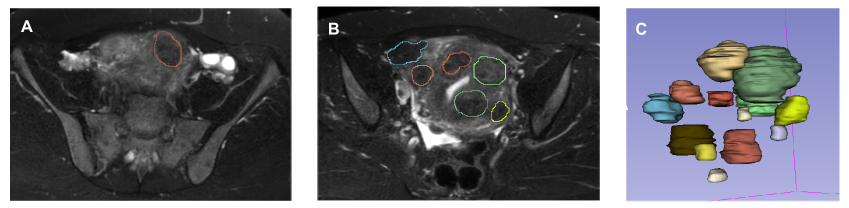

In the demonstration concerning fibroids, there are many of these problematic slices as the number of fibroids in one patient has a wide range (from 1 to 14 in our dataset), see an example on Fig. 6.

Refer to caption

Figure 6: Representative slices of a patient with 14 fibroids. In our dataset, the number of fibroids in one patient can vary from 1 to 14. In case of the patient with 14 fibroids, the number of masks in one slice ranges from 1 to 6. In some slices (see Panel A.), there is only one mask, but other slices may interfere with more fibroids, thus there are slices with six masks as well (see Panel B.). The T2W SPAIR axial MRI images with the segmentation masks, as well as the 3D reconstruction of the masks are shown in the images.